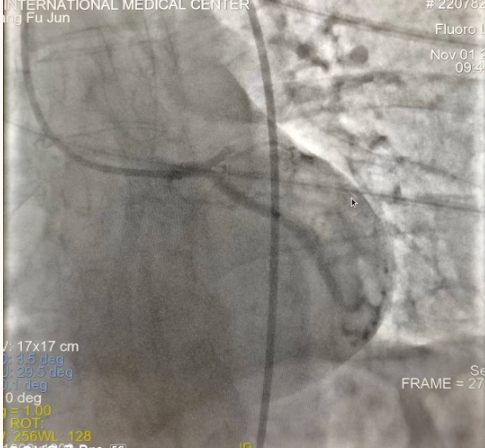

閉塞的血管再通時間取決于急救時長、轉(zhuǎn)運時長和治療時長,在前兩方面,醫(yī)院已為患者爭取了最短時間。患者家屬遠在陜北,雖然已在趕來的路上,但最快抵達西安也要3小時,在與患者家屬電話溝通同意急診手術(shù)后,醫(yī)療總值班代家屬簽字,康曉軍在請示心臟病醫(yī)院王海昌院長及心臟內(nèi)科CCU尚福軍主任后,積極進行術(shù)前準備。在沒有家屬陪同、沒有交費、沒有辦入院手續(xù)的情況下,患者經(jīng)胸痛中心綠色通道被送往心臟冠脈介入手術(shù)室,打通了完全閉塞的心臟前降支近段血管。